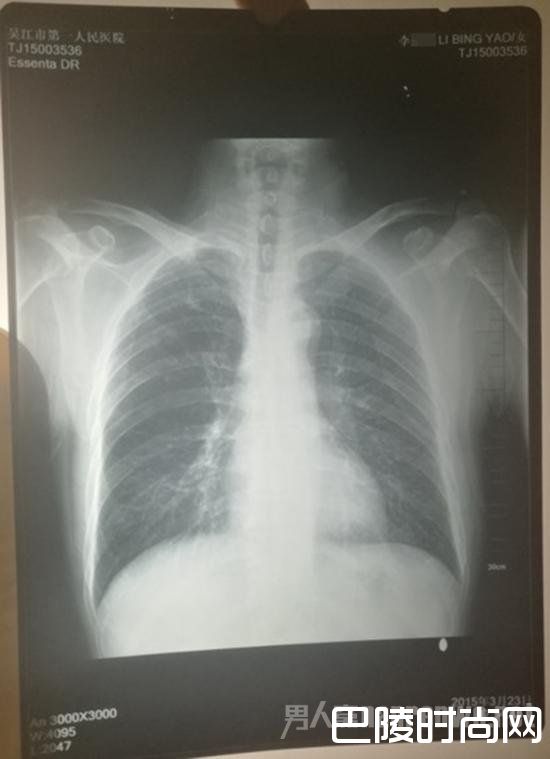

计建宏2015年3月23日在苏州市吴江区第一人民医院的体检报告显示,其放射科检查的结果小结为“心肺未见明显异常”。

此外,在报告结论中,写有“双肺纹理增多”并建议:请您戒烟、防止感冒,如有咳嗽、吐痰,请到内科咨询。

胸片